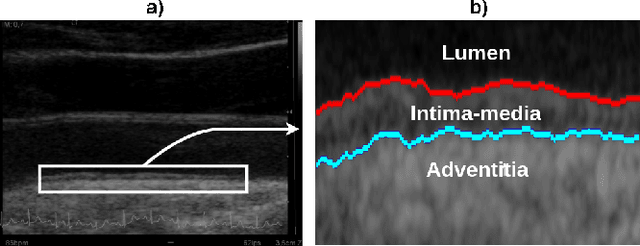

Abstract:The objective of this study is the segmentation of the intima-media complex of the common carotid artery, on longitudinal ultrasound images, to measure its thickness. We propose a fully automatic region-based segmentation method, involving a supervised region-based deep-learning approach based on a dilated U-net network. It was trained and evaluated using a 5-fold cross-validation on a multicenter database composed of 2176 images annotated by two experts. The resulting mean absolute difference (<120 um) compared to reference annotations was less than the inter-observer variability (180 um). With a 98.7% success rate, i.e., only 1.3% cases requiring manual correction, the proposed method has been shown to be robust and thus may be recommended for use in clinical practice.

Abstract:Purpose: The motion of the common carotid artery tissue layers along the vessel axis during the cardiac cycle, observed in ultrasound imaging, is associated with the presence of established cardiovascular risk factors. However, the vast majority of the methods are based on the tracking of a single point, thus failing to capture the overall motion of the entire arterial wall. The aim of this work is to introduce a motion tracking framework able to simultaneously extract the trajectory of a large collection of points spanning the entire exploitable width of the image. Method: The longitudinal motion, which is the main focus of the present work, is determined in two steps. First, a series of independent block matching operations are carried out for all the tracked points. Then, an original dynamic-programming approach is exploited to regularize the collection of similarity maps and estimate the globally optimal motion over the entire vessel wall. Sixty-two atherosclerotic participants at high cardiovascular risk were involved in this study. Results: A dense displacement field, describing the longitudinal motion of the carotid far wall over time, was extracted. For each cine-loop, the method was evaluated against manual reference tracings performed on three local points, with an average absolute error of 150+/-163 um. A strong correlation was found between motion inhomogeneity and the presence of coronary artery disease (beta-coefficient=0.586, p=0.003). Conclusions: To the best of our knowledge, this is the first time that a method is specifically proposed to assess the dense motion field of the carotid far wall. This approach has potential to evaluate the (in)homogeneity of the wall dynamics. The proposed method has promising performances to improve the analysis of arterial longitudinal motion and the understanding of the underlying patho-physiological parameters.